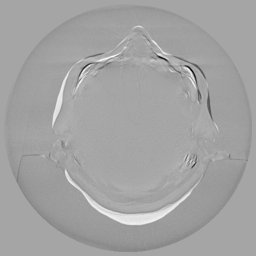

The results for simulated noisy data are shown in Fig. 2. The first and third rows display two representative slices from the test set, and the second and fourth rows present the corresponding error maps. The traditional WCE method suppresses cupping artifacts and recovers some missing anatomical structures but still shows noticeable deviations from the ground truth. Predictions from the four diffusion-based models demonstrate a markedly improved ability to restore anatomical structures. Among them, cDDPM fails to fully reconstruct the patient bed and retains residual noise in its outputs. This noise is attributable to an incomplete reverse denoising process rather than residual Poisson noise, as evidenced in our noise-free experiments (Fig. 5 in the Appendix). PatchDiffusion, diffusionGAN, and I2SB achieve similar visual quality, with I2SB producing the cleanest and most consistent reconstructions.

Quantitative results in Tab. V further confirm I2SB’s superiority over conventional deep learning methods such as FBPConvNet and Pix2pixGAN across RMSE, PSNR, and SSIM. Compared to other diffusion models—including cDDPM, PatchDiffusion, and cLDM—I2SB delivers higher image quality, while diffusionGAN achieves comparable quantitative performance. However, I2SB demonstrates a significant advantage in inference efficiency, as summarized in Tab. IV.